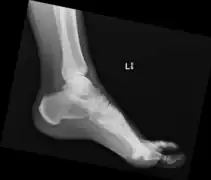

In some, the x-ray findings may correspond to symptoms of back stiffness with flexion/extension or with mild back pain.[2] Back pain or stiffness may be worse in the morning.[4] Rarely, large anterior cervical spine osteophytes may affect the esophagus or the larynx and cause pain, difficulty swallowing[5][6] or even dyspnea.[7] Similar calcification and ossification may be seen at peripheral entheseal sites, including the shoulder, iliac crest, ischial tuberosity, trochanters of the hip, tibial tuberosities, patellae, and bones of the hands and/or feet.[6]

Ectopic calcification and new bone formation in diffuse idiopathic skeletal hyperostosis (DISH)